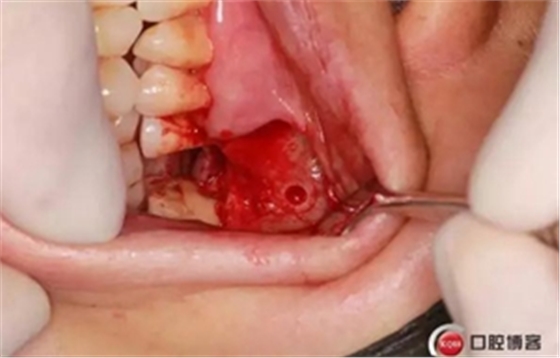

大家好,我是梁老師的助理小依。由于梁老師每天手術(shù)檔期安排較滿,加上經(jīng)常出差講課,沒有時間整理病例 。為了方便大家更及時的了解梁老師最新手術(shù)動態(tài),以后將由我為大家整理并推送梁老師最新經(jīng)典案例。案例文字旁白少,但圖片會盡量完整展示手術(shù)全過程,供大家學(xué)習(xí)參考。有任何問題,可以留言,梁老師會親自為大家解答。感謝大家對梁老師的支持和關(guān)注!